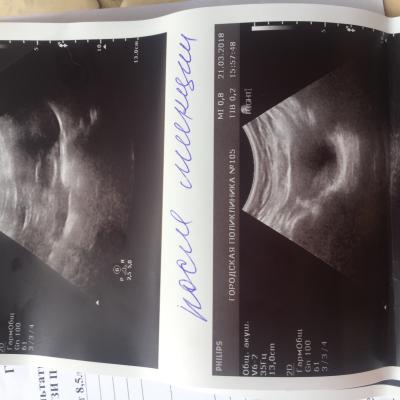

Здравствуйте. С Рождения гидронефроз левой почки , была удалена в декабре 2009 года. Анализы мочи и биохим анализ крови все показатели всегда в норме. Ребёнку 8 лет, сейчас одно УЗИ показывает размер почки 112 на 56, лоханка 16 мм. Другое узи сделанное через день показало: размер почки 78 на 30 , лоханка 7 мм. Паренхима на обоих узи 13 мм. Так же было сделано исследование УЗДГ почки ( все в норме, отклонений нет) Не можем понять почему такая разница по УЗИ где правда ? Как нам с этим разобраться .